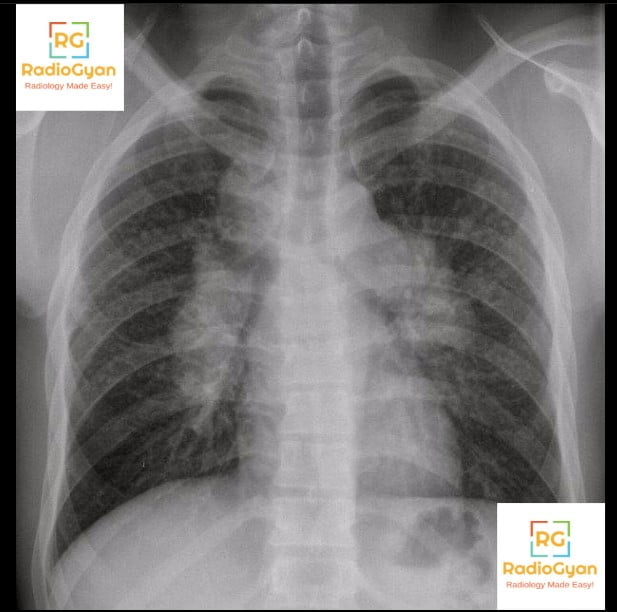

Pawnbrokerโs sign is caused by bilateral hilar and right paratracheal lymphadenopathy, most commonly seen in sarcoidosis. This pattern of lymph node enlargement on chest radiographs reflects granulomatous inflammation within the lymphatic system of the mediastinum and hila.

It is named “Pawnbrokerโs sign” because the lymph node enlargement pattern resembles the three suspended balls of the traditional pawnbrokerโs symbol, historically linked to the Medici family crest and symbolizing monetary lending. The three nodal groups (right paratracheal, right hilar, and left hilar nodes) seen on chest X-ray correspond visually to the three balls hanging from a bar in the pawnbrokerโs emblem.

The sign develops due to granulomatous infiltration and subsequent enlargement of mediastinal and hilar lymph nodes. Sarcoid granulomas accumulate within these nodes causing symmetrical swelling, which projects on chest radiographs as three distinct rounded opacitiesโright paratracheal, right hilar, and left hilar lymphadenopathyโthat mimic the appearance of three balls suspended from a horizontal bar. This triad of lymphadenopathy arises from inflammation-driven lymph node hyperplasia and fibrosis typical of sarcoidosis.